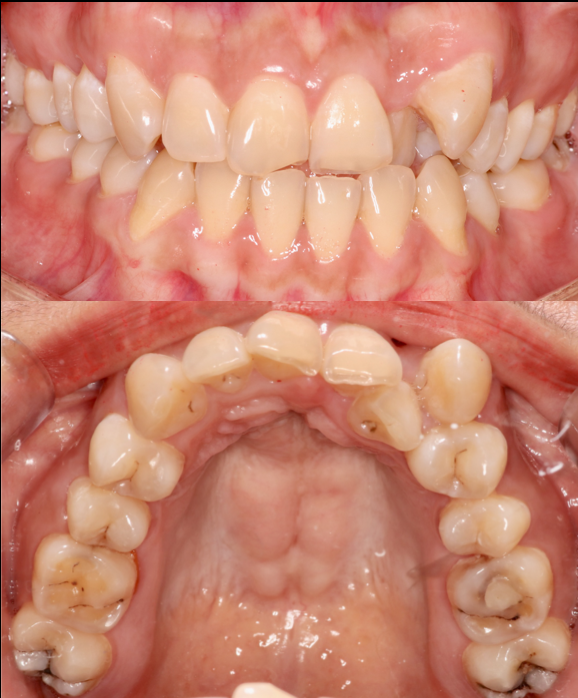

Before

After

All-on-6 in Atrophic Bone

This case involved a patient with severe periodontitis and advanced bone atrophy. Full upper arch rehabilitation was performed using the All-on-6 technique with 2 straight and 4 tilted implants to avoid the maxillary sinus. Immediate loading was done, and the final prosthesis was delivered after 6 months. Treatment successfully restored function and esthetics at Moral Dental Clinic.